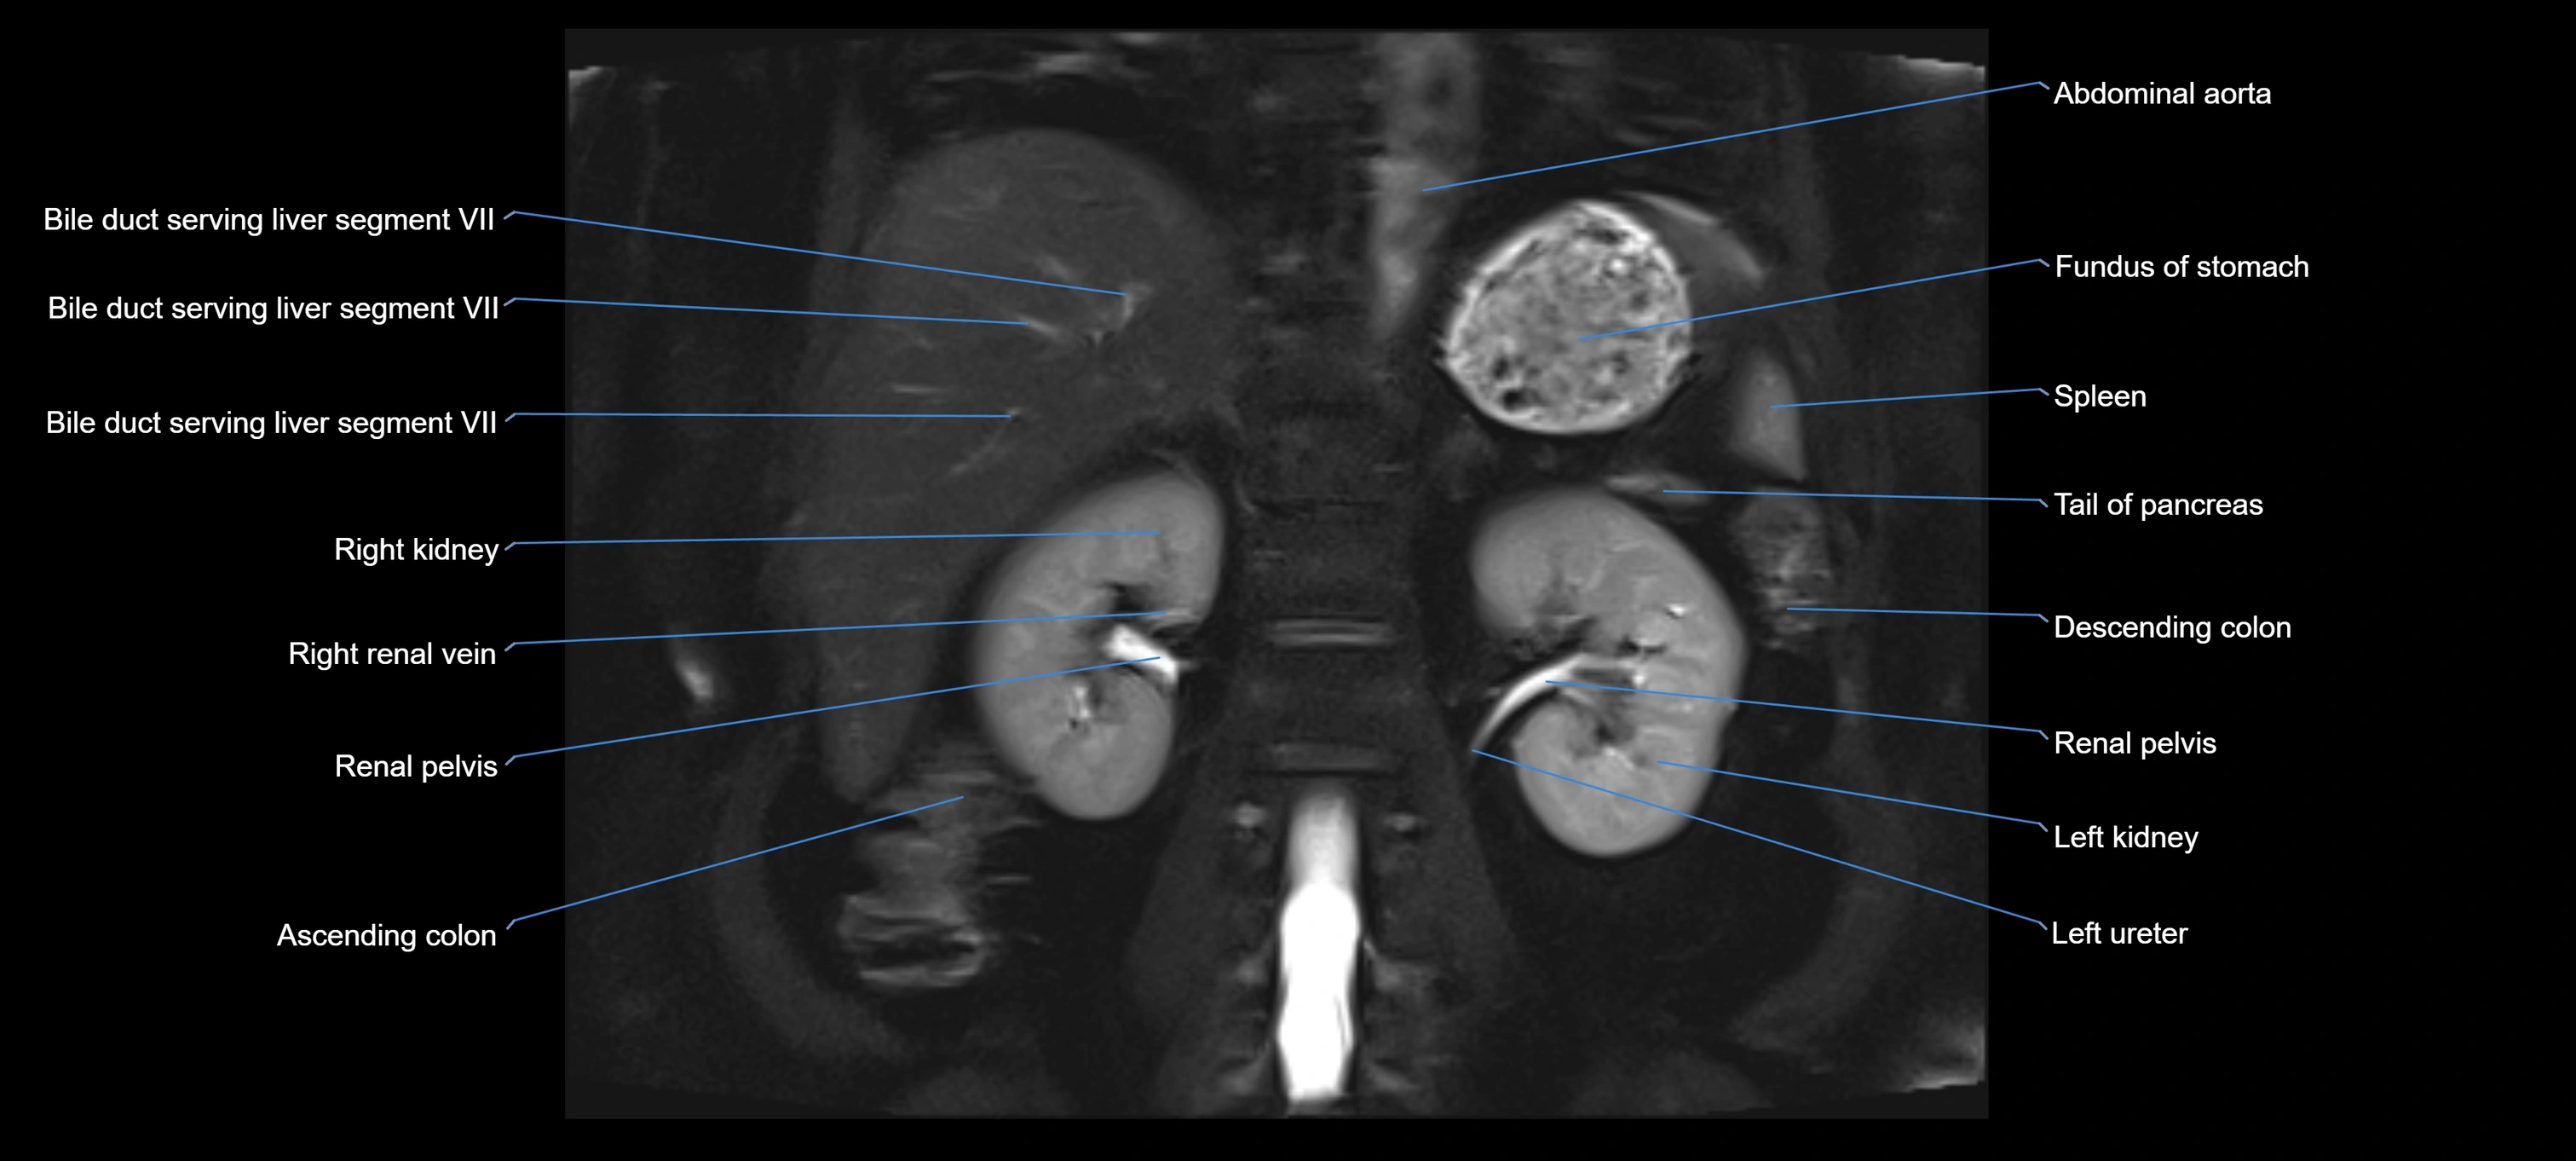

MRI image

image